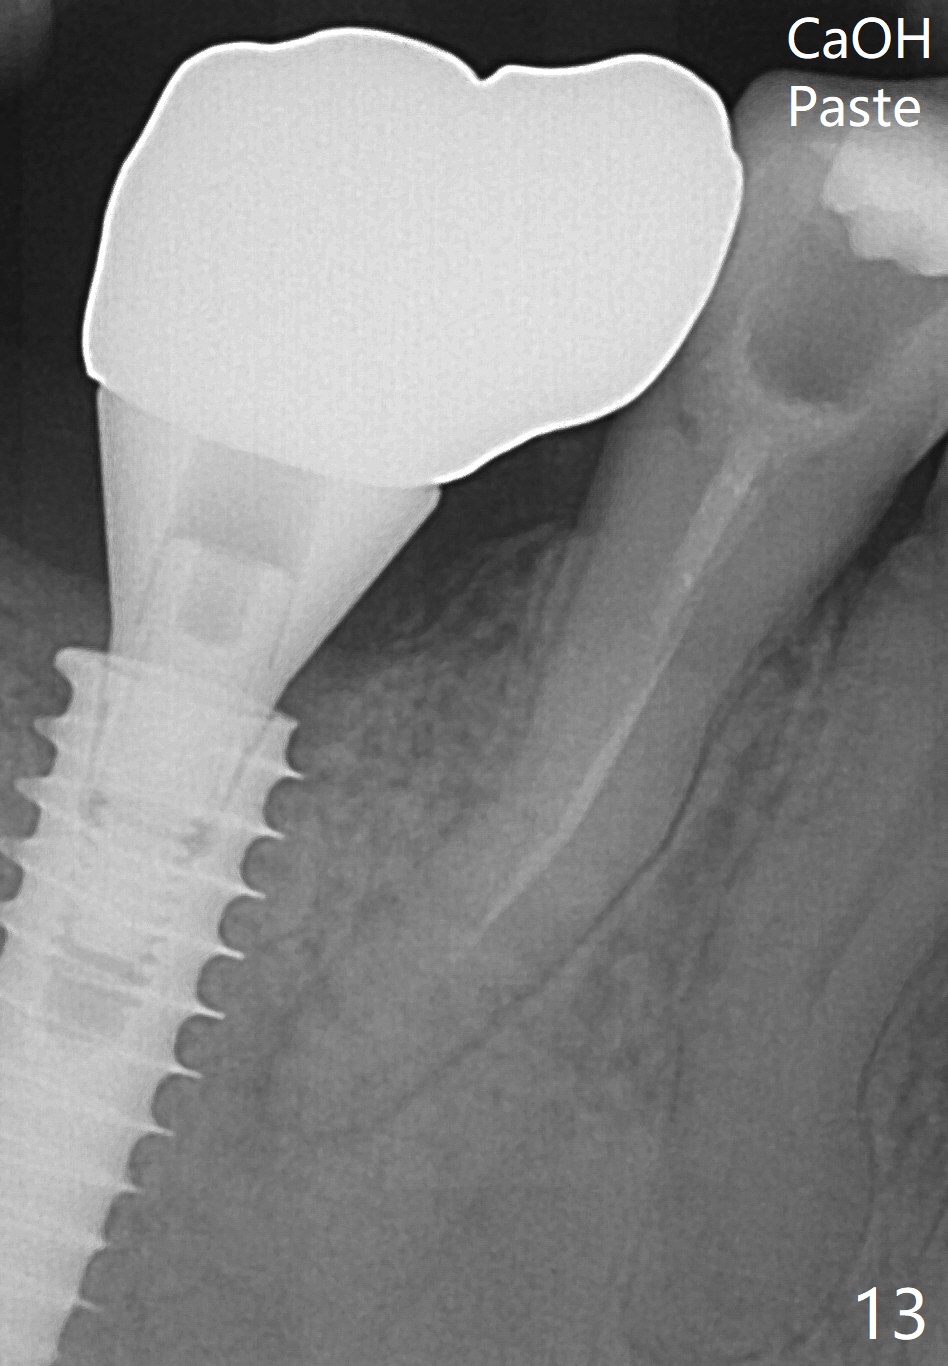

Bone graft seems to sink down and becomes denser 3 months postop (Fig.6 arrow). The bone continues being denser 5 months postop (Fig.7). There is periapical radiolucency of the tooth #29 (^). RCT is done (Fig.8). The pain persists 2 weeks postop (Fig.9,10). There is no missing canal (Fig.9). The apex is close to the implant (Fig.9 *). Apicoectomy will be performed if needed. It appears that the implant is also placed buccal (Fig.10 <) and/or the implant too large for the site. Therefore there should be a 2-3 mm buccal gap before and after implant placement. Separation and reflection of the buccal flap allows better visibility. The pain persists 1 month post RCT and 6 months post implant placement. RCT retreatment is initiated (Fig.11,12) with placement of Calcium Hydroxide paste after redebridement with 30/.04 rotary file at 23.5 mm (.5 mm longer than the earlier RCT, Fig.13). RCT retreatment finishes with apparent transportation and extrusion in 4 weeks (Fig.14,15), followed by apicoetomy (Fig.16,17) (20 days later)). Discomfort remains 2.5 months postop (Fig.18). Keep watching.